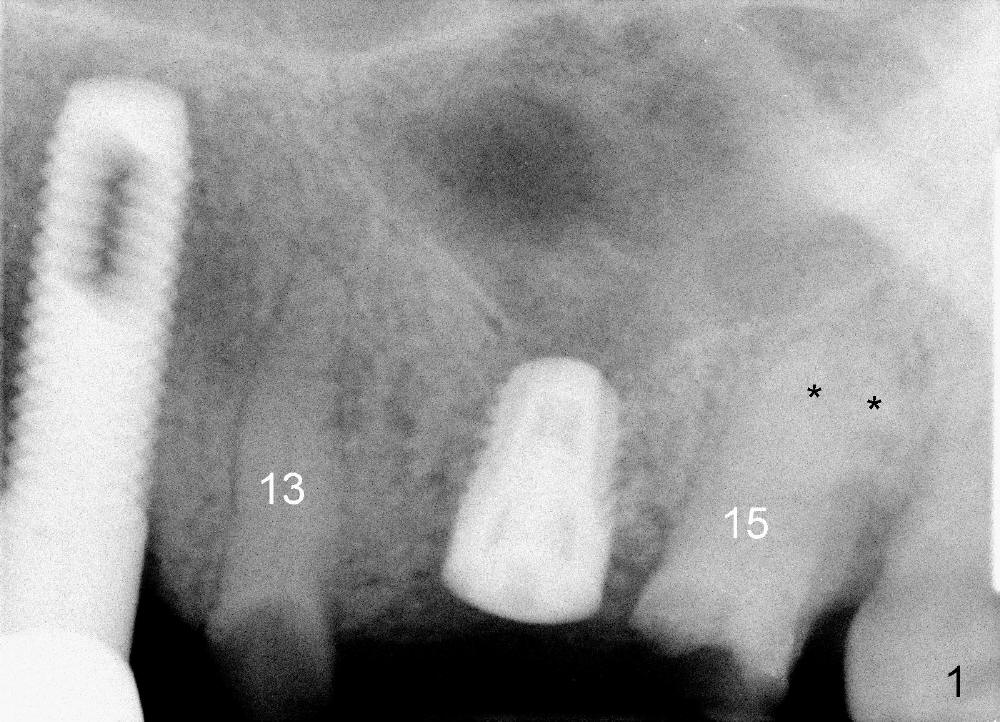

A 84-year-old man has a failing bridge.  A short implant was placed at the pontic site 5 months ago (Fig.1, taken 2 months postop).  The bridge was temporarily recemented.  It is planned at next appointment to extract #13, uncover the implant at pontic and save #15 if possible.  When the bridge is removed, the tooth #15 is also found non salvageable (Fig.2). The root stump of #15 is oval, 5x10 mm.  Preop PA shows that the 2nd molar has two roots (Fig.1: *).  When the tooth is extracted, the septum is found wide buccolingually (Fig.3: S, between the buccal (B) and palatal (P) sockets).  Osteotomy is formed in the septum with combination of drills and osteotomes, followed by insertion of taps (Fig.4).  Finally the osteotomy (Fig.5 O) in the septum (S) of #15 deviates into the buccal (B) socket.  When the implant is placed (Fig.6), it deviates buccally slightly (Fig.7).  The remaining sockets are filled by bone graft (Fig.7 G).  Immediate provisional bridge is fabricated after placement of abutments (A).  The main purpose of the provisional at early stage is to hold bone graft in place.  There is no occlusal contact with the opposing dentition,  Due to time constraint, the uncovering of #14 is postponed.  The provisional dislodges 2-3 days postop.  The patient returns for recementation 5 days postop; the sockets have initially healed (Fig.8,9, as compared to Fig.7).

The implant crown at #15 becomes loose with pain and radiolucency around the implant (Fig.15 *) 2 years 2 months post cementation.  The implant is removed without difficulty.  The site is closed with Osteogen plug.  Next visit use RTs 2-4 to extend the osteotomy for 3-6 mm, followed by tapered taps.  If stability is low, change to cylindrical taps.  Place a 6x20 or 7x17 or 20 mm implant.